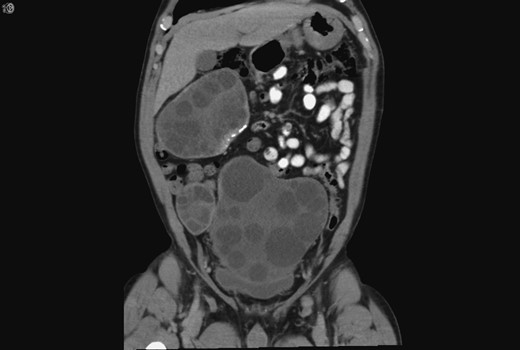

A 59-year-old Bosnian male presented with abdominal discomfort. A 20 × 10 cm2 suprapubic mass was palpable. An abdominal ultrasound scan (US) revealed a large complex pelvic mass, subsequent abdominal and pelvic computed tomography (CT) revealed multiple complex peritoneal cysts suggestive of hydatid disease (Fig. 1).

Coronal CT showing the hydatid cysts with daughter cysts within the larger structures.

As a child he reported frequent contact with livestock and dogs. Upon military conscription, aged 17, investigations revealed a pulmonary mass, resection of which confirmed echinococcosis. Five years later, he was diagnosed with splenic hydatid disease culminating in splenectomy. The multiple large cysts and daughter cysts now seen on his CT were presumed secondary to spillage and peritoneal seeding of hydatid cysts during his splenectomy 37 years prior.